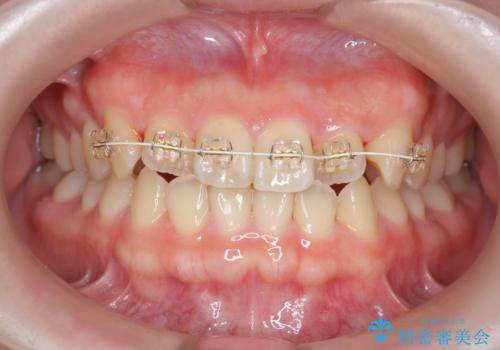

前歯のねじれを改善 小矯正+マウスピース矯正インビザライン

- 「前歯のねじれ、見た目を改善したい。」と矯正治療を希望され来院されました。

マウスピース矯正では改善の難しい前歯のねじれを前歯の部分ワイヤー矯正で改善したのち、インビザライン矯正を行い歯列を整えます。

インビザラインを行う前に前歯の部分矯正を行ったことで、しっかりとねじれが取れ整った歯列へと仕上げることが出来ました。